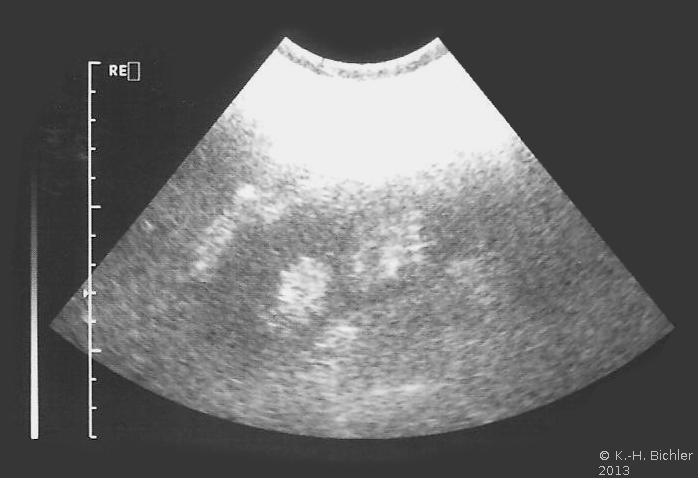

Die asymptomatische doppelte Nierenanlage wird bei sonographischen bzw. röntgenologischen Untersuchungen meist zufällig entdeckt (Abbildung 3) (

s. Bildgebende Verfahren).

Die symptomatische Doppelniere (z.B. bei Harnwegsinfekt) erfordert den Einsatz bildgebender Verfahren. Ausgehend von der Sonographie sind Ausscheidungsurogramm, Computertomogramm bzw. retrograde Sondierung des fehlgebildeten Anteils erforderlich. Fehlgebildet sind in der Regel die obere Hälfte des gedoppelten Organs bzw. die separate Niere ("Nierenknospe"). Der dysplastische Nierenanteil zeigt oft nur schwache bzw. keine Kontrastmittelausscheidung.